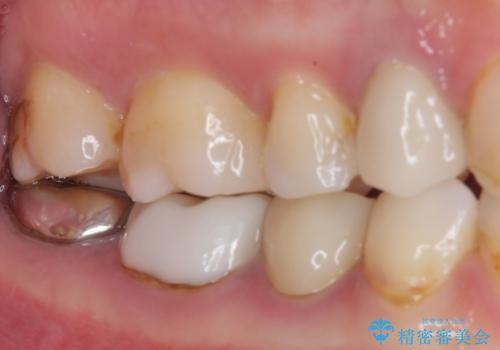

- 奥歯の詰め物や周辺の歯が欠けてしまったとのことで来院された患者様です。

上顎は、元々の詰め物が小さく、欠けた範囲も大きくなかったため、セラミックインレーにて修復治療を行うこととしました。

一方下顎は、元々のむし歯の範囲が広かったため、長期的な予後を踏まえ、セラミッククラウンにて補綴治療を行うこととしました。